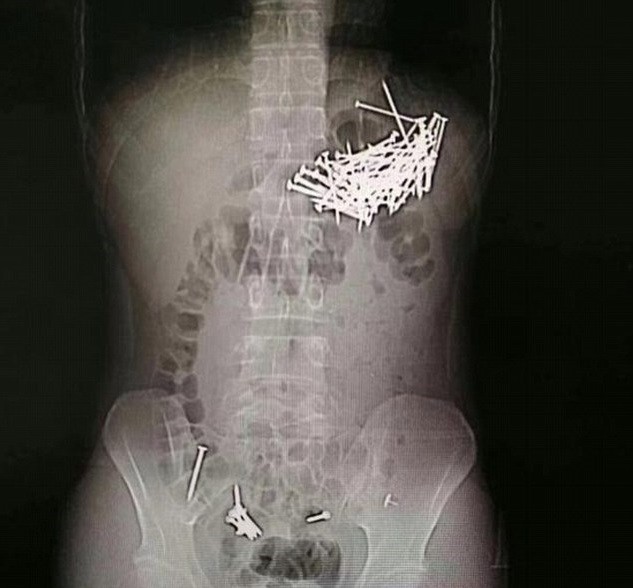

لكن الأطباء عرفوا ما حصل معه تماما بعد أن أجروا له صورة أشعة سينية. وأخضعوه لعملية جراحية لاستخراج المسامير، استغرقت 4 ساعات. وتمكن الأطباء من استخراج 87 مسمارا تتراوح أطوالها ما بين 4 و5 سنتيمترات.

وعرف أطباء المستشفى أن الشاب بلع المسامير بعد مشكلة مع صديقته التي هددت بهجره. ويتعافى الشاب الصيني في المستشفى بعد أن ابتلع "صدفة" مسامير الحب القاتلة.